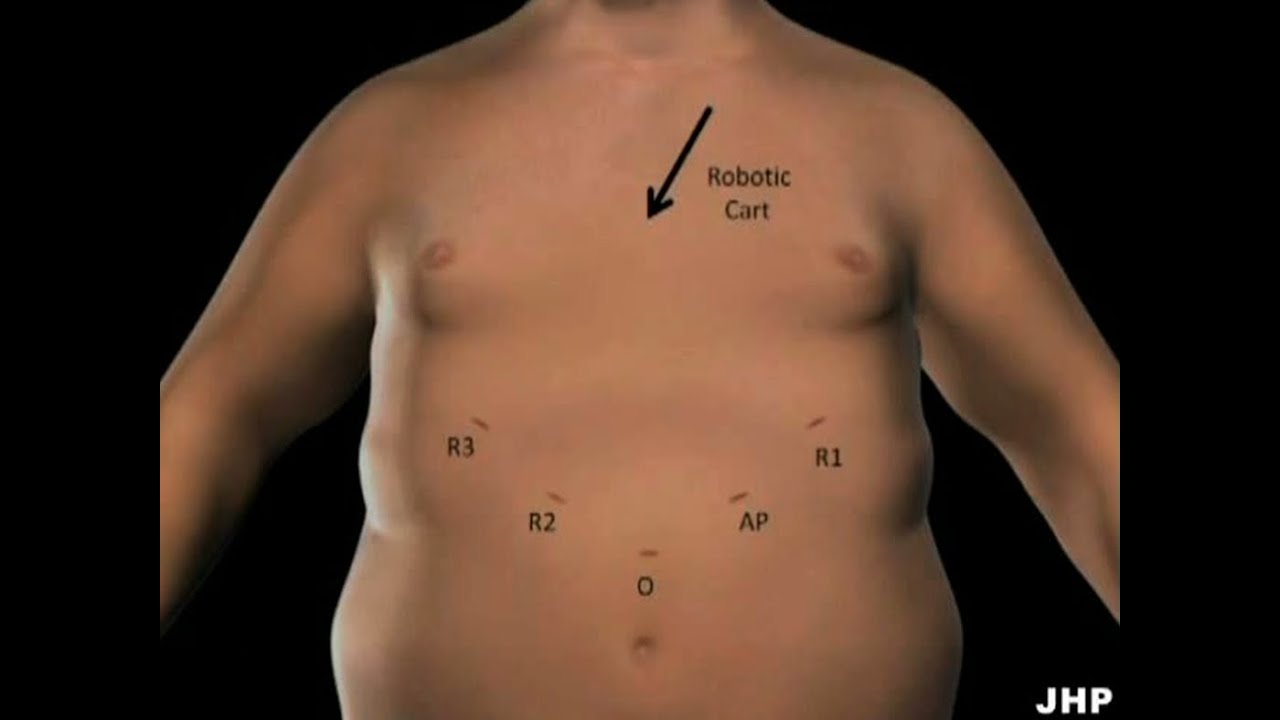

Operating Room Set Up

Wellbeing ';